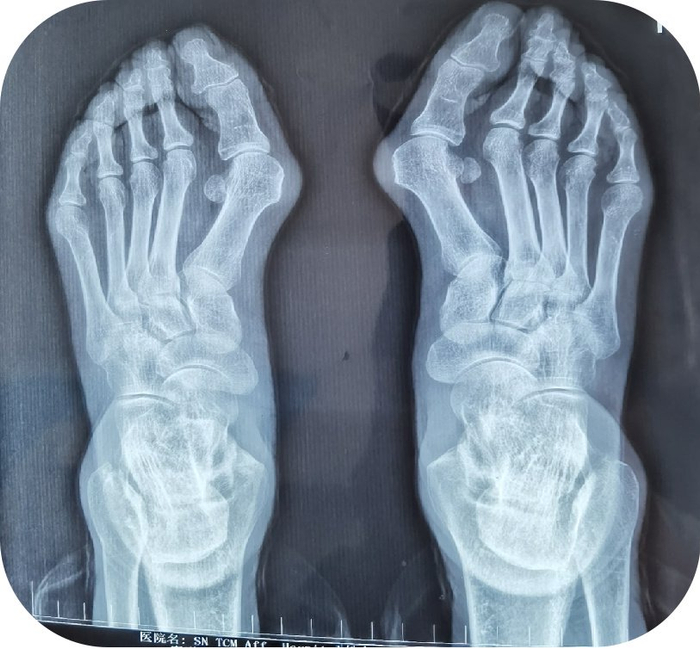

陕西中医药大学附属医院:夏季即将来临,告别大脚骨,秀出足部美|附属